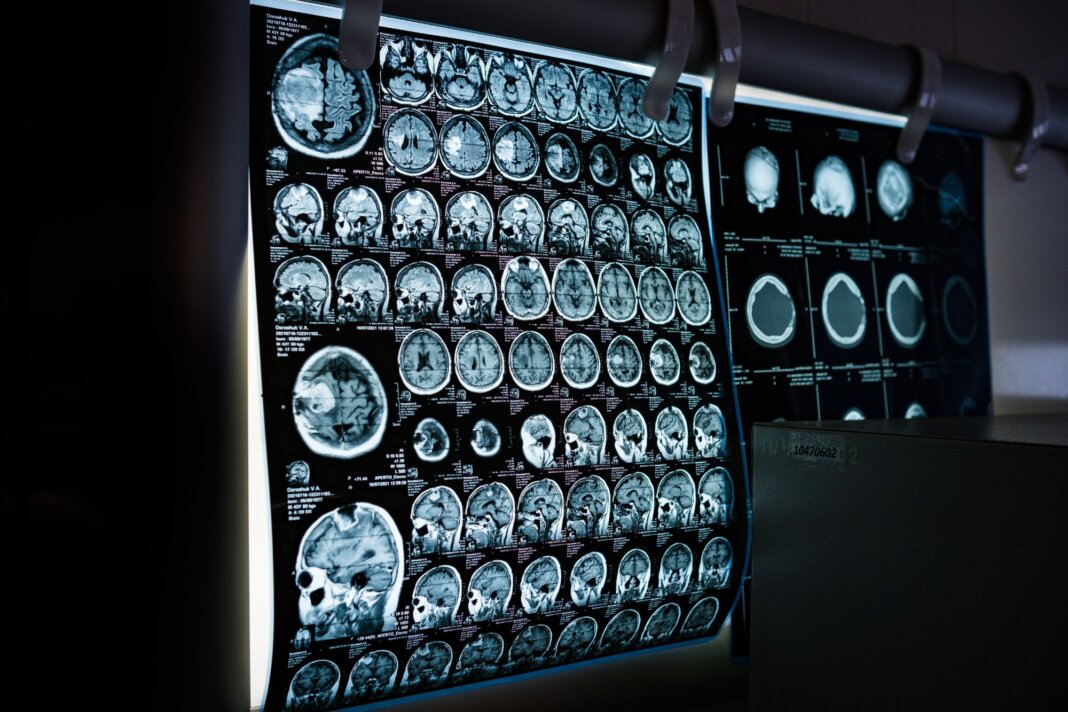

Lo studio, guidato da Alex R. DeCasien del National Institute of Mental Health, rappresenta una novità per le neuroscienze. I ricercatori hanno analizzato circa 1,2 milioni di cellule provenienti da sei diverse regioni della corteccia cerebrale di 30 donatori. Grazie a tecnologie di trascrittomica, la disciplina biologica che studia l’insieme completo degli Rna messaggeri presenti in una cellula, tessuto o organismo a singola cellula, il team ha potuto osservare l’attività di 680.000 neuroni eccitatori, 290.000 neuroni inibitori e centinaia di migliaia di cellule gliali, le instancabili “assistenti” del cervello.

Il risultato è una mappa ad altissima risoluzione che identifica dove e come i cromosomi sessuali e gli ormoni lasciano la loro impronta molecolare.